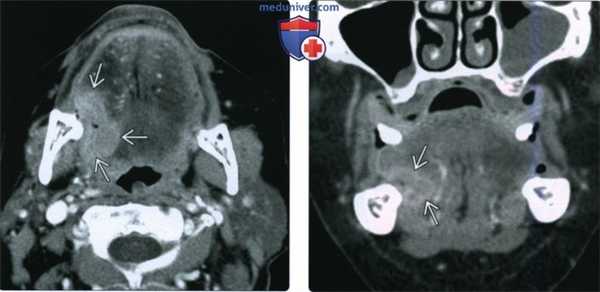

(Слева) На изображении показан ПКР альвеолярного гребня нижней челюсти с распространением на тело нижней челюсти (Т4а). Обратите внимание на инвазию нижнего альвеолярного нерва - момент, важный для полной резекции опухоли.

(Справа) При аксиальной КУ с КУ визуализируется объемное образование неоднородной структуры, разрушающее тело нижней челюсти слева. Опухоль распространяется кнаружи между десной и щекой, прорастая в щеку, а также кнутри, прорастая в дно полости рта. Опухоль (T4aN1) была полностью удалена, дефект тканей закрыт комбинированным лоскутом. (Слева) На фото у мужчины 66 лет виден патологический очаг В неправильной формы с уплотнением и изъязвлением тканей в области альвеолярного гребня верхней челюсти, начинающийся на уровне первого премоляра. Была выполнена биопсия, подтвердился инвазивный плоскоклеточный рак. Клинически стадия была определена как T2N0.

(Справа) При МРТ Т1ВИ в аксиальной проекции у этого же пациента определяется мягкотканный компонент снаружи от альвеол нижней челюсти; жировая ткань (по сравнению с противоположной стороной) отсутствует. На томограммах не определяется убедительных признаков инфильтрации костного мозга, что позволяет выполнить частичную максиллэктомию.